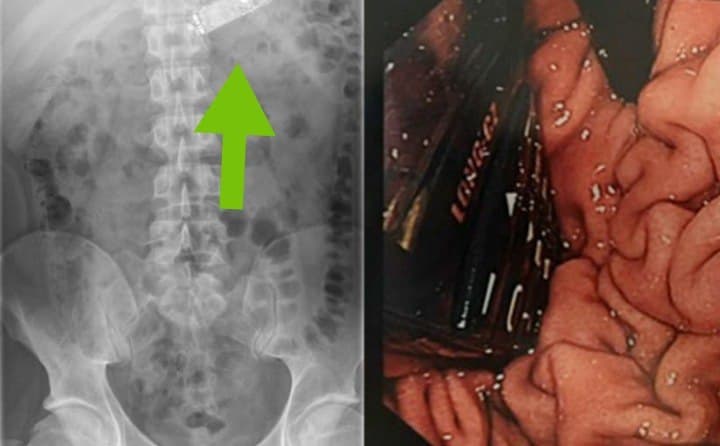

ब्रिटेन में एक शख्स के पेट से डॉक्टरों ने मोबाइल फोन निकाला। शख्स ने 6 महीने पहले गलती से मोबाइल फोन निगल लिया था। इसकी उसे खुद भी जानकारी नहीं थी। लगातार पेट दर्द की शिकायत और हालत बिगड़ने पर वह डॉक्टर के पास गया। डॉक्टर ने एक्सरे कराया और इसे देखकर हैरान रह गए। फिर शख्स का ऑपरेशन किया गया और मोबाइल निकाला गया। फिलहाल मरीज की हालत ठीक है।

मीडिया रिपोर्ट के मुताबिक, 33 वर्षीय शख्स के पेट का ऑपरेशन मिस्र के असवान यूनिवर्सिटी अस्पताल में हुआ। हालांकि, मरीज के पेट से मोबाइल फोन निकलेगा, डॉक्टरों को इस बात का बिल्कुल भी अंदाजा था। फिलहाल ये नहीं पता चल पाया है कि मरीज ने मोबाइल को कैसे निगल लिया था।

ऑपरेशन को अंजाम देने वाली मेडिकल टीम का नेतृत्व करने वाले डॉक्टर स्केंडर तेलजाकू ने गुलाबी रंग के नोकिया 3310 फोन की तस्वीरें साझा की जिन्हें मरीज के पेट निकाला गया था।